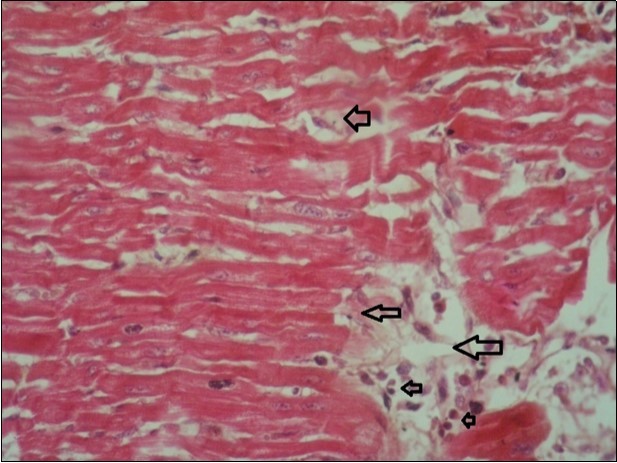

Figure 11.heart (dead cattle less than 1 year old) showed vesicular nuclei of myocytes which suffering hydropic degeneration. Some inflammatory cells (neutrophils, esinophils, lymphocytes) substitute an area of necrosis inside myocardium bundles (arrows). (H &E, X 40)

heart (dead cattle less than 1 year old) showed vesicular nuclei of myocytes which suffering hydropic degeneration. Some inflammatory cells (neutrophils, esinophils, lymphocytes) substitute an area of necrosis inside myocardium bundles (arrows). (H &E, X 40)